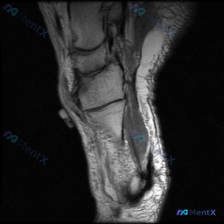

给大家分享一例有意思的足部MRI读片病例,一开始锁定的方向是「软骨异常」,但完整读片下来发现真正的问题其实在别的地方,整理了整个思路分享给大家。 一、病例影像基本信息 这是一张足部矢状位T1加权MRI,图像对比度尚可,清晰显示了后足(跟骨、距骨)、中足(舟骨、楔骨)及部分前足结构,可以明确识别跟骨、...